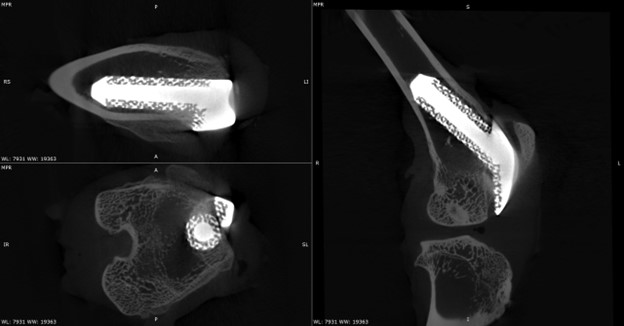

High‑resolution micro-CT enables the non‑destructive, 3D visualization of implants and surrounding bone over time. The images presented here showcase the use of micro-CT to study periprosthetic joint implantation and osseointegration in rabbit models, allowing tracking of implant positioning, bone remodeling, and early indicators of bone integration at multiple time points.

Below are micro-CT reconstructions of a femoral implant in a rabbit knee model. High-resolution imaging enables tracking of implant position and progressive changes at the implant-bone interface over time.

Temporal Assessment of Implant-Bone Interactions

Micro-CT imaging allows repeated scanning of the same implanted joint, providing a powerful means to observe temporal changes in bone architecture without disrupting the tissue. These scans allow monitoring of how the surrounding trabecular and cortical bone adapts to the presence of the implant, capturing subtle changes in bone volume, density, and structure as healing progresses. This approach enables precise comparison of early versus later stages of implant integration within the rabbit knee.